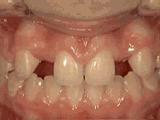

1、龅牙,前牙突出,个别牙齿扭转,通过专业评估,上下两侧各拔牙一颗后,经过矫正是变成这样的~

2、牙列不齐,牙齿异位,咬合关系紊乱,影响正常发音和正常咀嚼,经过矫正后是变成这样的~

3、牙齿拥挤,个别牙异位,牙弓狭窄,导致局部牙齿重叠生长,两侧各拔牙一颗后,经过矫正是变成这样的~

4、牙列拥挤,前牙没有咬合,上下牙齿中线不对称,牙弓狭窄,上颌“*牙虎**”异位生长,经专业评估没有拔牙,经过矫正后的牙齿是这样的~